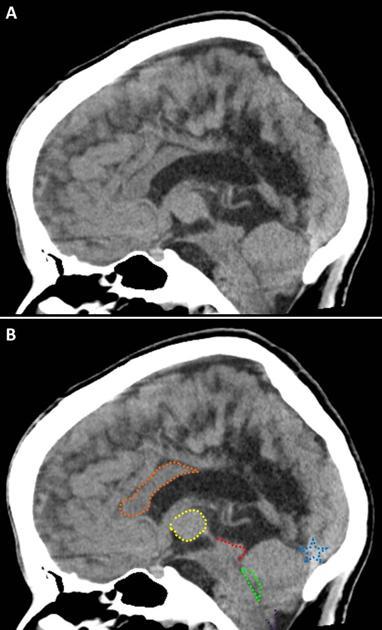

Diagnosis?

Imaging findings?

Dysgenesis of the corpus callosum- partial or complete absence of the corpus callosum.

High-riding 3rd ventricle, Bundles of Probst (tracks of white matter that run parallel to the ventricle as an alternative to the CC- thats why the lateral ventricles are farther apart), “bullhorn” appearance of the frontal horns, absent cingulate sulcus, absence of the septum pellucidum or severe widening of the cavum septum pellucidum, enlarged occipital horns (colpocephaly).

Associated with otehr CNS anomalies.